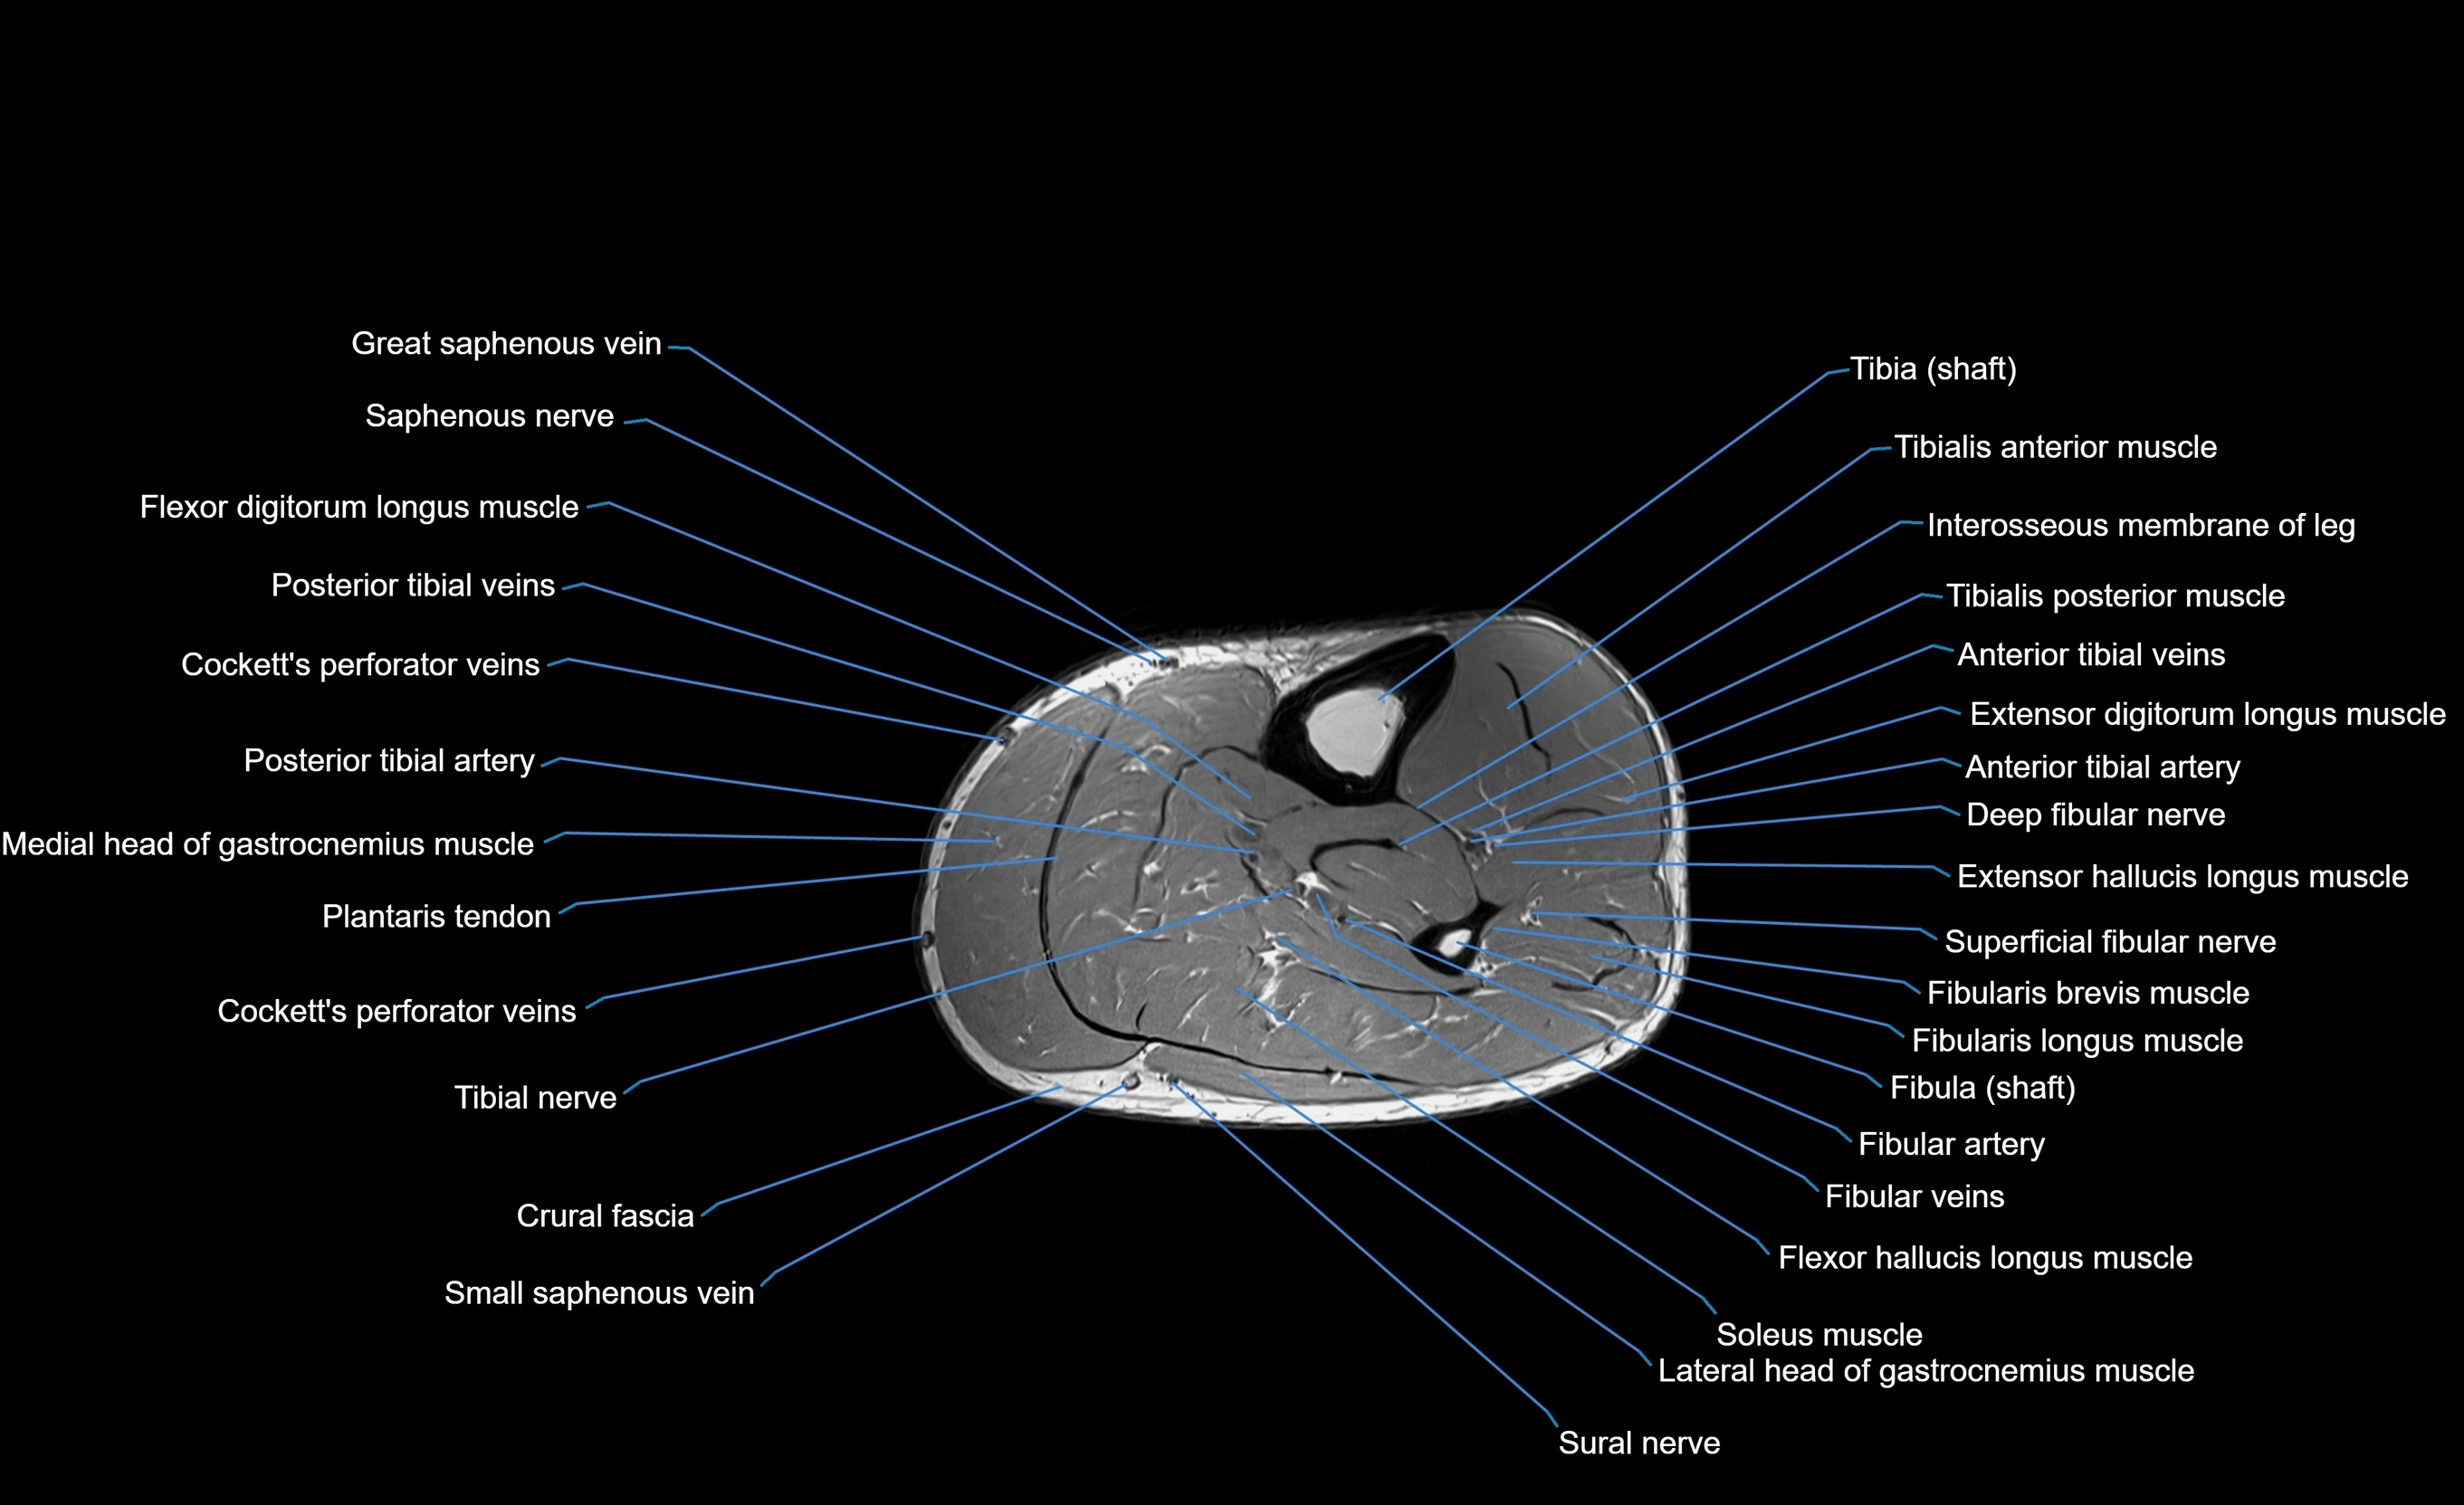

MRI image